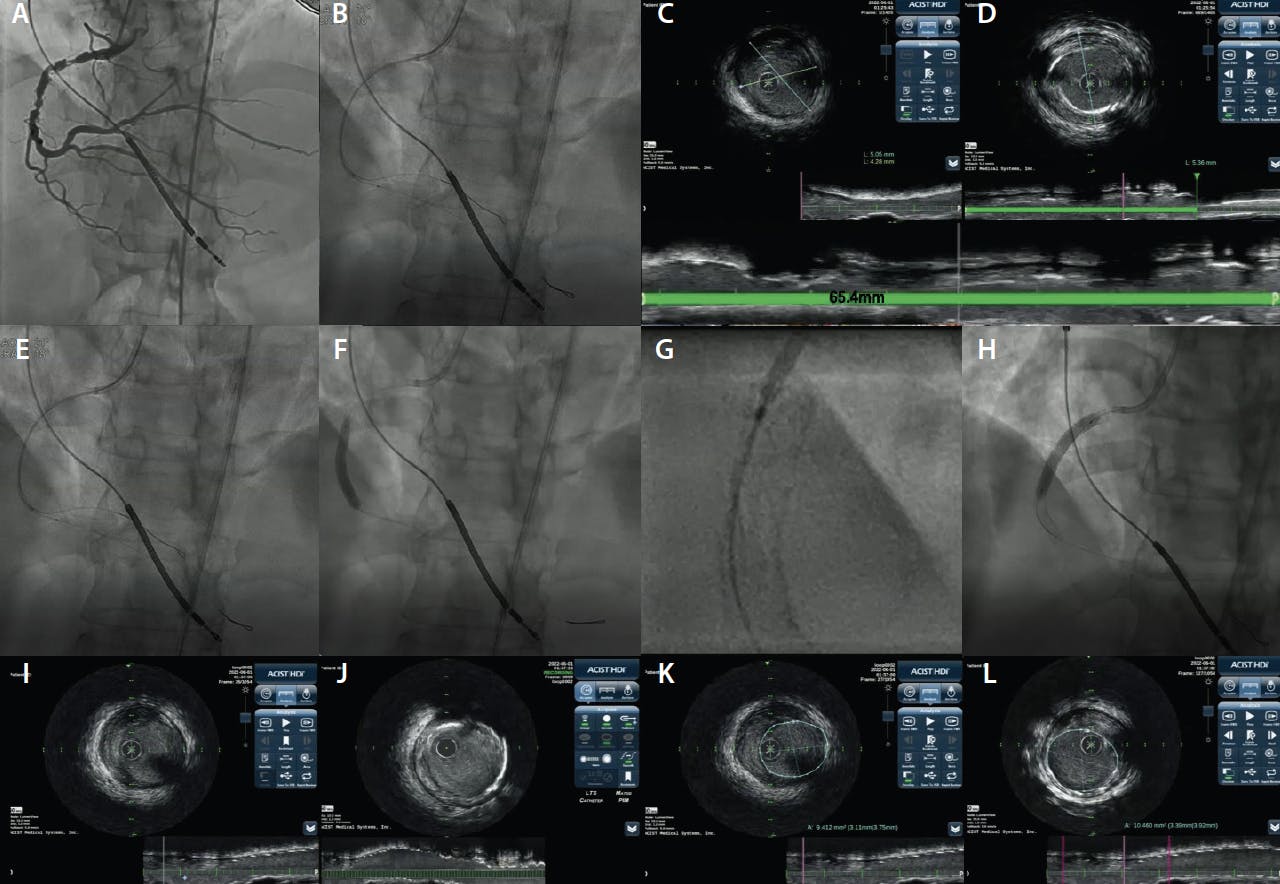

“Zero-contrast” PCI, which is typically a staged procedure in non-ACS patients, is a strategy for PCI without using, or drastically minimizing, contrast in late-stage CKD. The previously performed ULCA serves as the blueprint or roadmap.4 Staging the procedure allows for a reduction in the total contrast exposure, recovery of kidney function, and discussion of the risks and benefits of zero-contrast PCI with the patient. Previously obtained diagnostic angiograms are displayed and used as a roadmap for guide catheter engagement and guidewire advancement. The shapeable tips of the guidewire are typically looped whenever possible to decrease the chances of distal vessel perforation. Use of several guidewires is recommended to generate a metallic silhouette or coronary skeleton of the target vessel and its branches (Figure 3 and Figure 4). The procedure is then guided by intravascular imaging (ultrasound4 or optical coherence tomography with saline flush8) with or without coronary physiology. Coregistration of physiology and intracoronary imaging pullback with the wire silhouette allows for contrast-free localization of flow-limiting stenoses, vessel segments that require plaque preparation, optimal stent landing zones, and choosing stent size and length. After stent implantation, the same approach can be followed to verify the results of PCI or to guide optimization, also with the use of stent enhancement tools, all without the need for contrast injections. Prespecified criteria indicating procedural complications or suboptimal results are devised to guide the use of contrast to perform angiography during the zero-contrast procedure, if indicated.4 These include unresolved electrocardiogram changes or symptoms, hemodynamic instability, failure of physiological parameters to improve, or the presence of a new effusion on echocardiography (Figure 1).

Figure 4. Zero-contrast PCI in a patient with advanced CKD. A roadmap from a previously performed ULCA of the right coronary artery with 3 mL of contrast in the LAO-cranial view is projected (A). A reference segment distal to the lesion is identified manually and marked with cine angiography (B). By coregistering the intravascular ultrasound pullback with the angiogram, reference vessel measurements are obtained at the distal reference segment, revealing a mean distal vessel size of 4.6 mm (C). Following the same approach, a proximal, disease-free segment is identified: The length of lesion measured from the distal reference to this segment (green line) is 65.4 mm and the mean proximal vessel size is 5.3 mm (D). The stent is then deployed using manual intravascular ultrasound co-registration marking (E), where the distal stent marker is aligned to the intravascular ultrasound transducer and a 4.5-mm X 38-mm drug-eluting stent is deployed (F). Given a total stent length of 65 mm, and the distal deployment of a 38-mm stent, the proximal stent is determined to be a 5-mm X 28-mm device. High-magnification cine angiography, or preferentially advanced features such as StentBoost (Philips), StentViz (GE Healthcare), or Device Detection (Philips), are used to confirm optimal overlap (G). The proximal 5-mm X 28-mm stent is deployed (H). The distal (I) and proximal (J) stent edge were free of dissection. Stent expansion was confirmed by measuring the distal reference area (9.4 mm2) (K) and comparing it to the manually identified minimal stent area (10.4 mm2) confirming > 100% expansion (L).

An initial report in 35 patients with eGFR 16 ± 8 mL/min/1.73m2 supported the feasibility and safety of this approach, resulting in preserved postprocedural kidney function in all patients and no need for RRT.4 A prospective, single-center, propensity-matched comparison with standard angiography alone showed that combined ULCA and zero-contrast PCI was associated with a significant reduction in the rates of RRT within a 12-month follow-up period (hazard ratio, 0.40; 95% CI, 0.21-0.75; P = .0032).9 Given the frequent presence of severe calcification, atherectomy may be needed during zero-contrast PCI to modify the fibrocalcific plaques and optimize PCI results.10 The recent advent of intravascular lithotripsy, which is a balloon catheter-based technique, may simplify calcific plaque modification as part of zero-contrast PCI.11 The feasibility of zero-contrast PCI has also been shown in complex lesions (such as chronic total occlusions12 and high-risk PCI with hemodynamic support13 or in vein grafts14). Randomized studies are warranted to further establish the role of ULCA and zero-contrast PCI as part of the invasive management strategy for coronary artery disease in late-stage CKD.